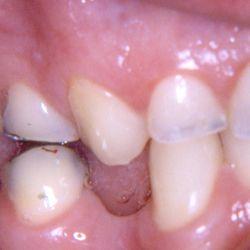

Ο προγόμφιος της φωτογραφίας υπέστη κάταγμα του παρειακού φύματος λόγω εκτεταμένης παλιάς έμφραξης αμαλγάματος.

Προκειμένου να αποφευχθεί ο τροχισμός του δοντιού για τοποθέτηση στεφάνης, διαδικασία που μπορεί να οδηγούσε σε νέκρωση του δοντιού, αποφασίστηκε η αφαίρεση της παλιάς έμφραξης αμαλγάματος και η αποκατάσταση του δοντιού με ένα επένθετο εργαστηριακής σύνθετης ρητίνης.

Ο εκτροχισμός που απαιτήθηκε για αυτή την διαδικασία ήταν ελάχιστος, έτσι το δόντι διατηρήθηκε ζωντανό χωρίς προβλήματα.